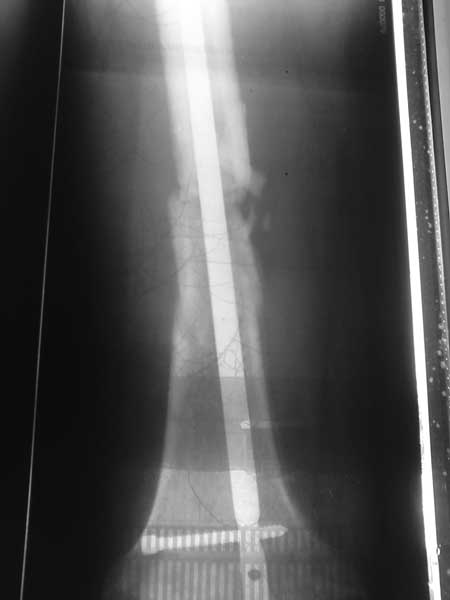

И, еще раз, надо снимок на всем протяжении бедра, как уже сказано выше - и сколенным, и с тазобедренным суставами. Без снимка не догадаться, где заканчивается вверху стержень, где располагаются какие винты.